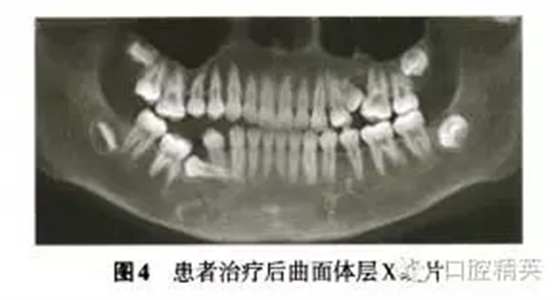

診斷:安氏Ⅲ類亞類錯牙合畸形,5V、5V阻生。治療方案:①拔除V,V,清理V囊腔;②牽引5至正常牙列;③試牽引5,不排除牽引失敗的可能;④使用種植體支抗防止鄰牙壓低和對牙合牙伸長;⑤糾正右側后牙開牙合,若654粘連導致正畸治療無效,則需調(diào)整治療方案。拔除埋伏乳磨牙時,錐形束CT確認下頜神經(jīng)管位于阻生V根分叉下方(圖3),5牙根位于43舌側。手術順利拔除埋伏阻生的V、V,8個月后曲面體層x線片示牙槽骨愈合良好,可見4顆第三磨牙牙胚(圖4)。但患者家長放棄牽引治療。